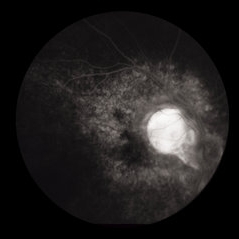

Ocular Toxocariasis slide 1

Ocular Toxocariasis slide 1

Oct 22 2012 by Ronald C. Gentile, MD

8-year-old boy with a history of puppy exposure failed his school screening in the right eye. Fundus examination revealed a old scarred granuloma involving the macula. Serum testing for anti-Toxocara antibodies were positive.

Photographer: The New York Eye & Ear Infirmary Department of Medical Imaging

Condition/keywords: scarred granuloma, toxocariasis